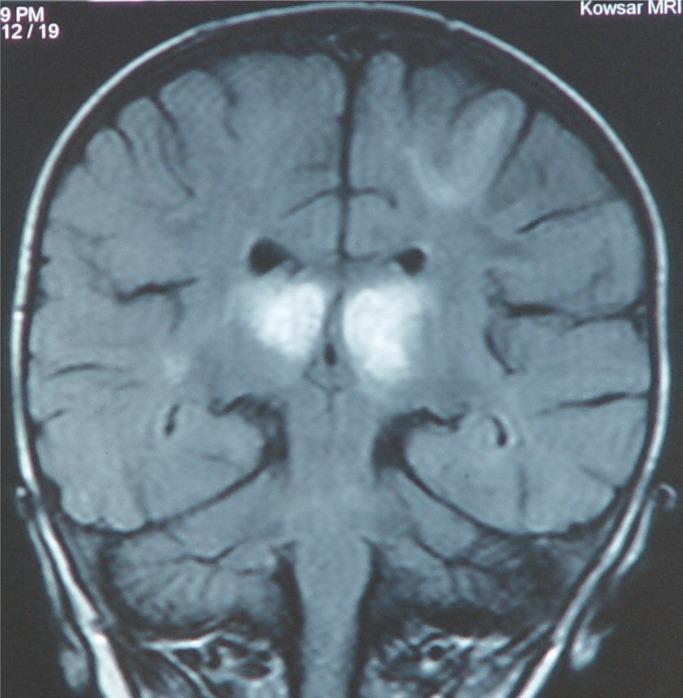

Acute Necrotizing Encephalopathy of childhood (ANEC) is a specific type of encephalopathy. After viral infection, it can be diagnosed by bilateral symmetrical lesions predominantly observed in thalami & brainstem of infants & children. Although, it is commonly occurred in Japanese and Taiwanese population. The goal of this article is to report a rare case of ANEC in a 15 months old girl infant from Thaleghani Hospital, Ramian, Gorgan, northern Iran.

儿童急性坏死性脑病(ANEC)是一种特殊类型的脑病。病毒感染后,可通过婴幼儿丘脑和脑干主要出现的双侧对称性病变进行诊断。尽管该病常见于日本和台湾地区人群。本文的目的是报告伊朗北部戈尔甘拉米安的塔莱哈尼医院一名15个月大女婴患ANEC的罕见病例。